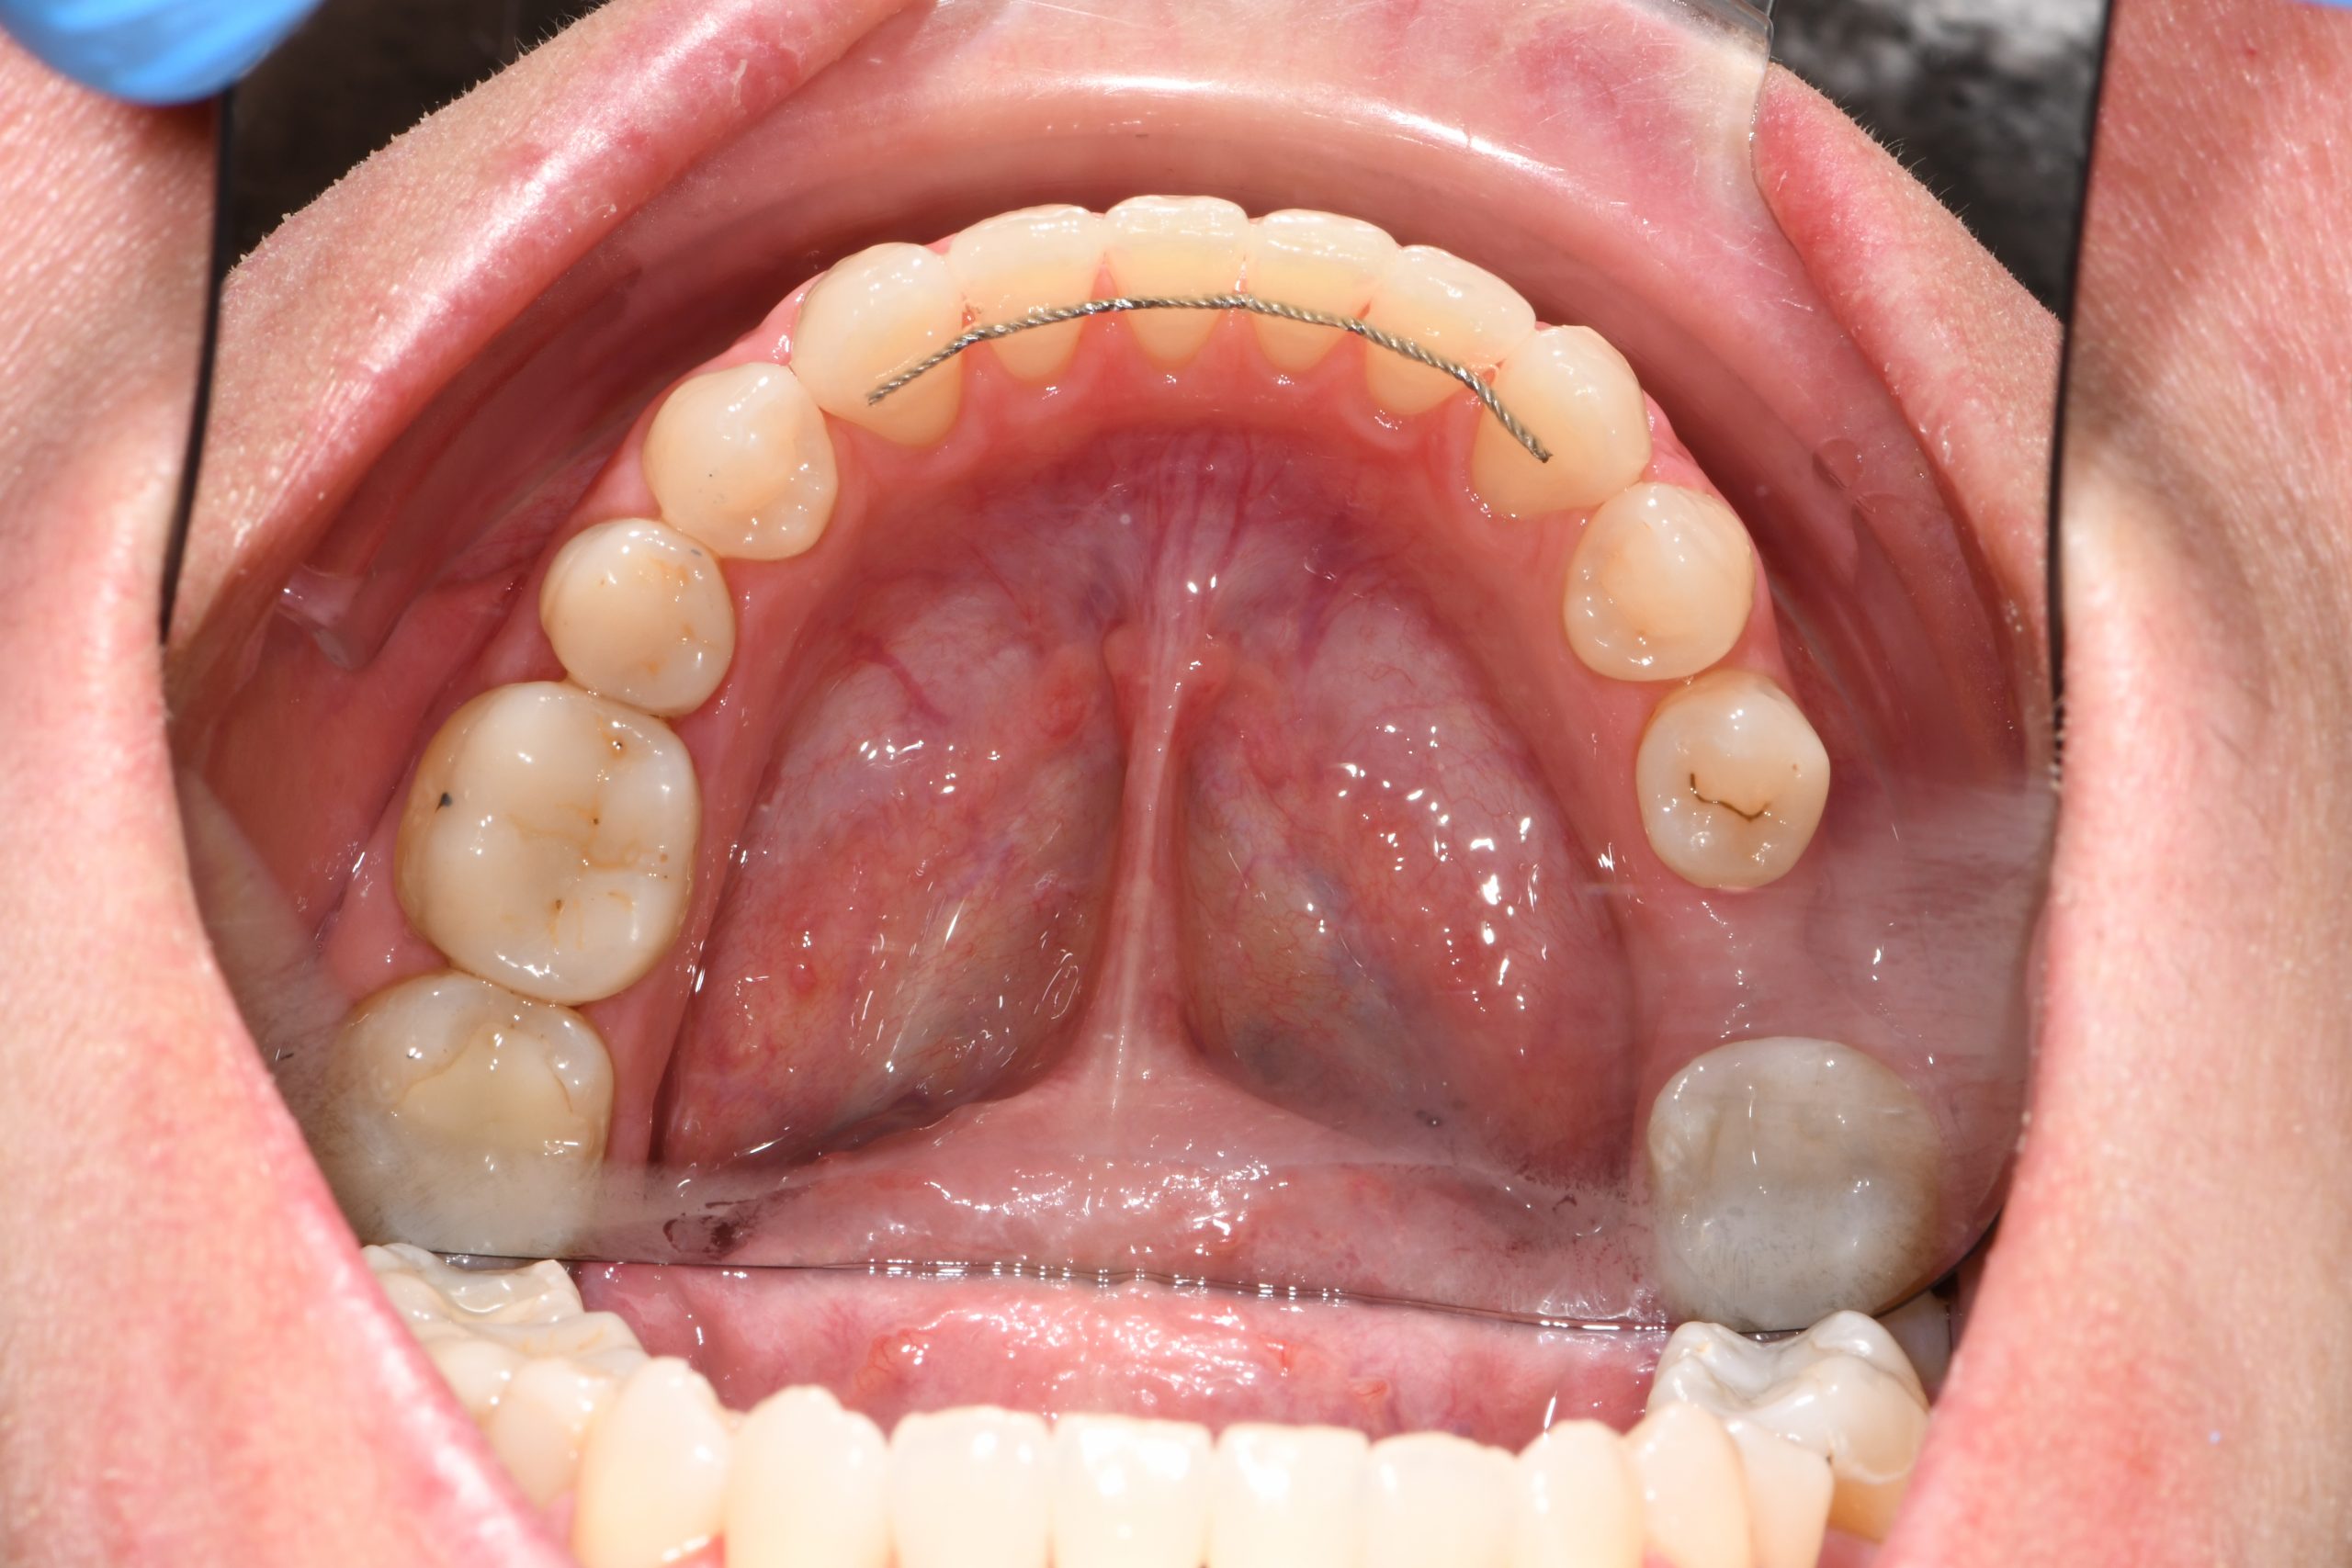

Az elmúlt évekből rengeteg szakmai referenciát tudnánk bemutatni, amelyek különböző fogszabályozási problémákat oldottak meg. Válogatva a több száz esetből, ezen az oldalon olyan képeket, információkat igyekeztünk bemutatni, amelyeknek a segítségével a jövőbeni pácienseinknek azt tudjuk üzenni: A Te fogsorod is lehet gyönyörű!

(Képeket a Pácienseink külön írásos beleegyezésével mutatjuk be!)